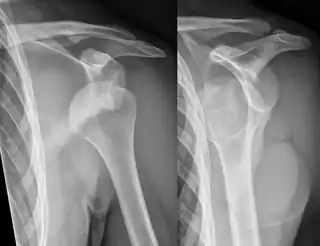

En medicina, una luxación o dislocación es aquella lesión de una articulación en la que se produce pérdida del contacto entre las superficies articulares. Generalmente se debe a un traumatismo grave y no existe fractura ósea, aunque en ocasiones se asocia la luxación a una fractura.[1] La luxación escápulo-humeral o luxación de hombro tiene lugar cuando por un movimiento brusco o un trauma se produce la pérdida de contacto entre la cabeza del húmero y la cavidad glenoidea situada en la escápula. Los dos extremos óseos se desplazan de su posición normal en continuidad y la articulación pierde su función. Representa el 50% del total de las luxaciones y se manifiesta por dolor muy intenso de inicio brusco que se acompaña de imposibilidad casi total para realizar los movimientos normales del hombro.[2]

Dependiendo de la dirección en que se desplaza la cabeza del humero, puede existir una luxación anterior que representa más del 80% de los casos, una luxación posterior que no es habitual y puede pasar inadvertida durante un tiempo al provocar síntomas menos llamativos y una luxación inferior que es muy rara.[2]